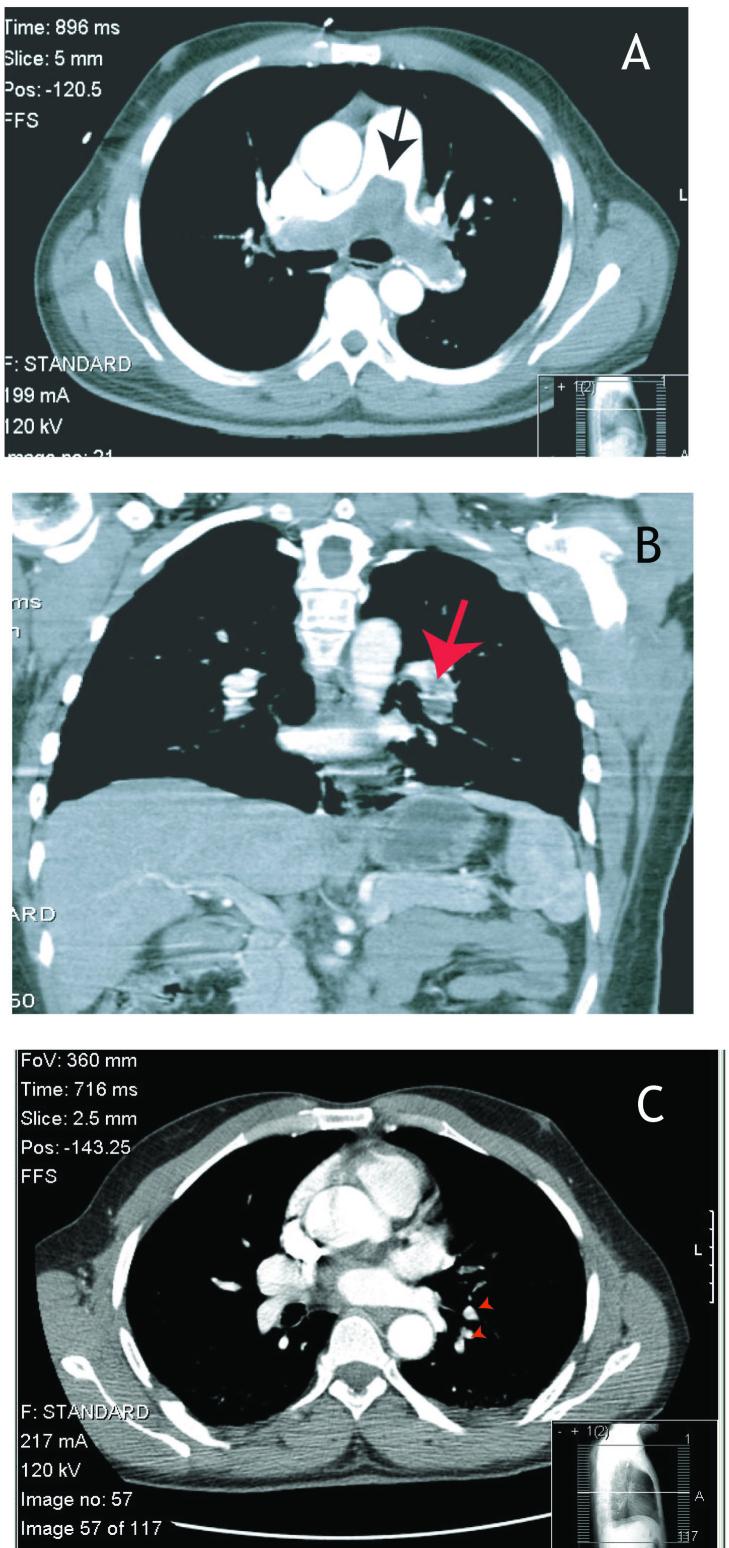

Pulmonary embolism (PE) is a life-threatening condition that may present as dyspnea, chest pain, cough or hemoptysis, but often occurs without symptoms. It is not typically associated with hiccups. Hiccups are generally self-limiting benign contractions of the diaphragm that may be associated with medications or food but may also be symptomatic of serious disease when persistent. We report 3 cases of PE presenting as persistent hiccups.

肺栓塞(PE)是一种危及生命的疾病,可能表现为呼吸困难、胸痛、咳嗽或咯血,但常无症状。它通常与打嗝无关。打嗝通常是膈肌的自限性良性收缩,可能与药物或食物有关,但当持续存在时也可能是严重疾病的症状。我们报告了 3 例以持续打嗝为表现的 PE。